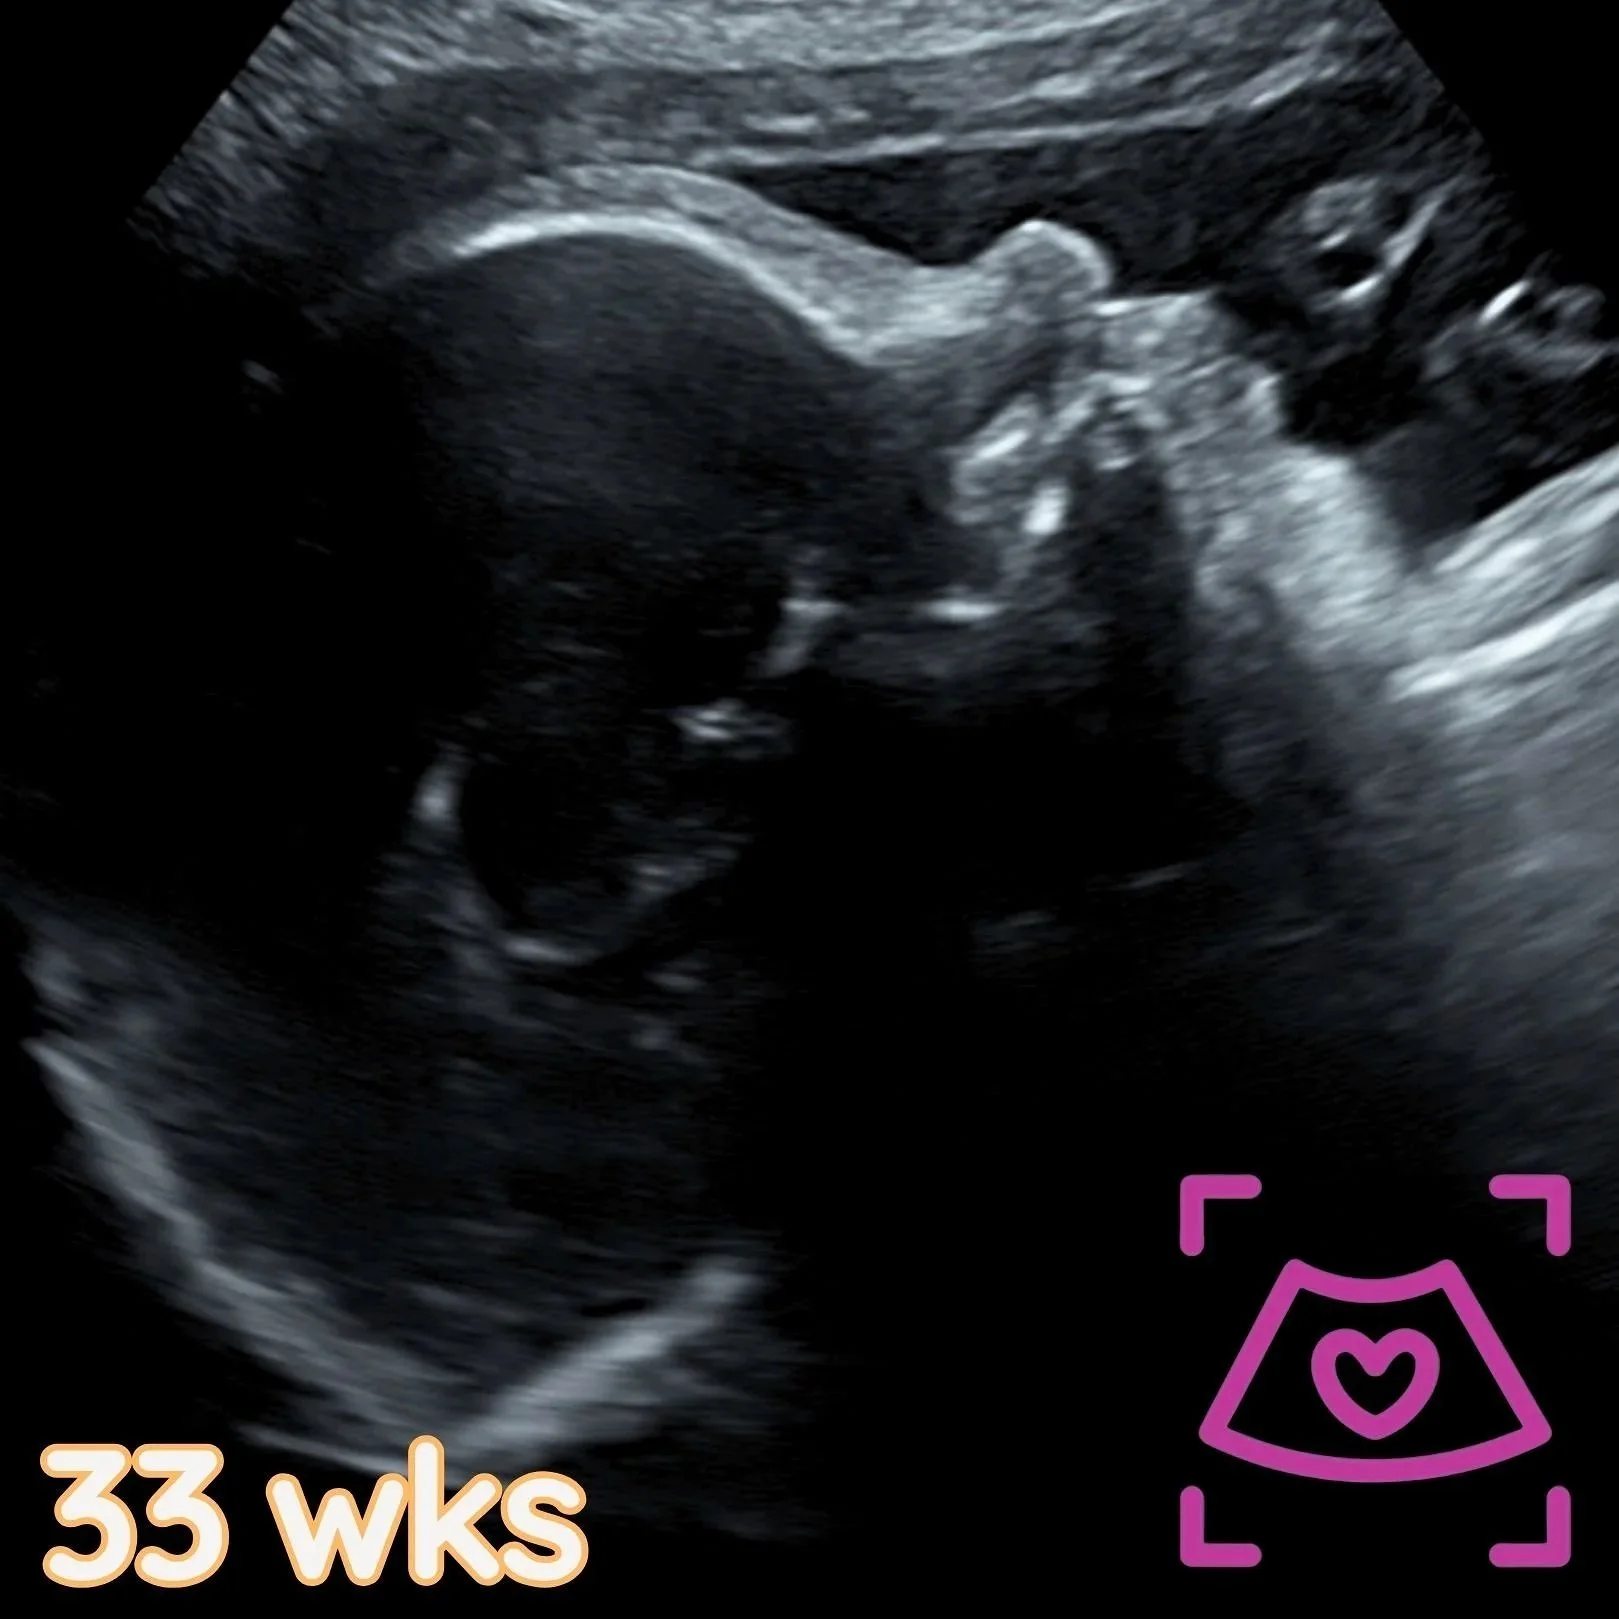

Performed after 32 weeks @ Baby Haven without NST.

This detailed ultrasound evaluates your baby’s overall well-being in the third trimester. Results are sent to your provider for review and follow-up care. Printed photos and a digital gallery are included. -